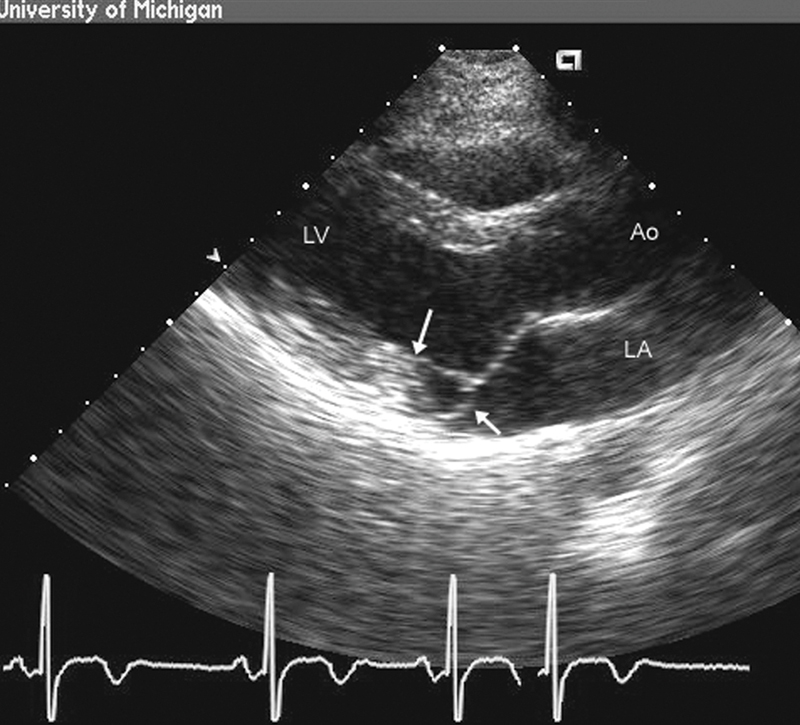

فحوصات تشخيصية لبعض امراض القلب والشرايين التاجية